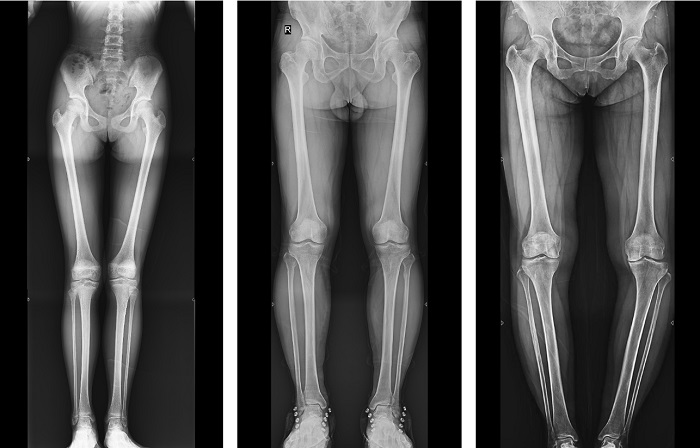

全脊柱成像對于脊柱側(cè)彎的診斷治療、手術(shù)方案的制定具有重要的參考價值;全下肢成像對于髖關(guān)節(jié)、膝關(guān)節(jié)角度的測量、髖和膝關(guān)節(jié)矯形手術(shù)、人工關(guān)節(jié)置換術(shù)等具有重要的參考價值,同時在創(chuàng)傷外科、康復科患者的檢查、診斷和治療中也發(fā)揮著重要作用。

▲全下肢DR影像